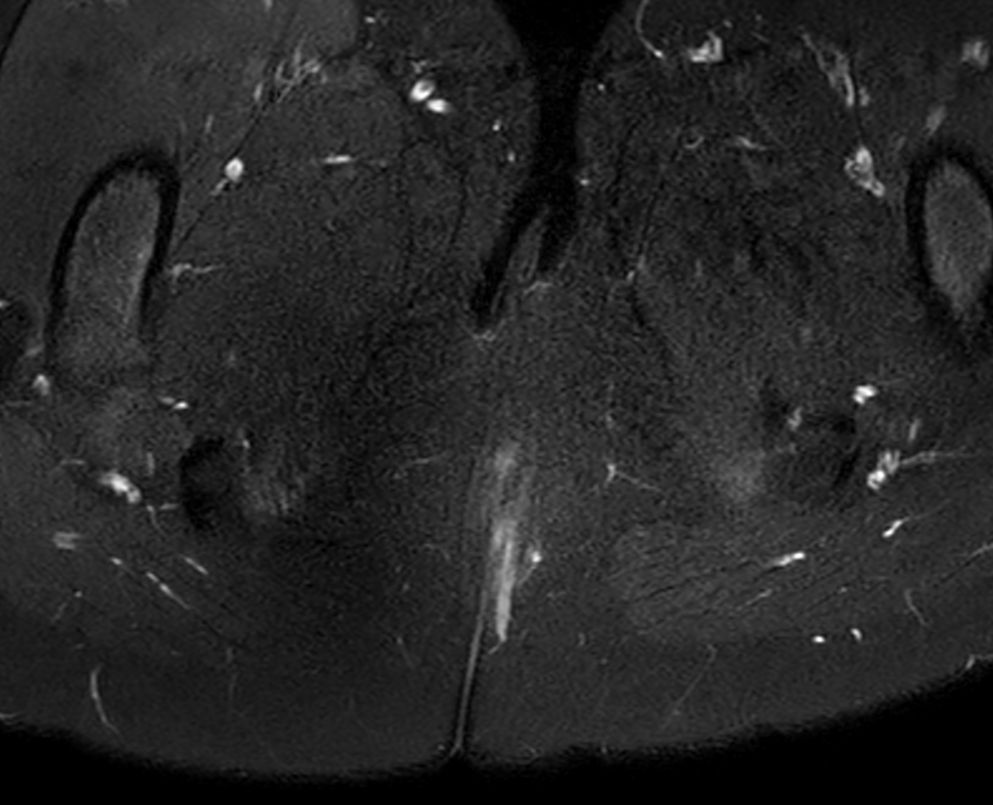

8 years old pediatric patient with a fistula in the pelvis. MultiVane XD is used to achieve high resolution diagnostic images, even in the case of severe patient motion. Integration of Compressed SENSE acceleration technique enables speeding up of the entire exam.

Axial T2w FatSatCompressed SENSE